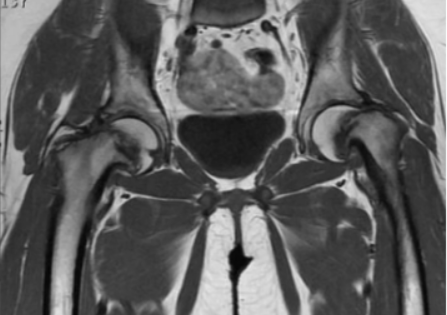

Эпифизеолиз бедер на МРТ

Магнитно-резонансная томография и компьютерное сканирование являются дополняющими способами диагностики, так как часто необходимо оценить и мягкотканные структуры и кости, формирующие сустав. В экстренных ситуациях преимущество у КТ, позволяющей получить результат в течение нескольких минут. Отдаленные последствия травм, опухоли, аваскулярный некроз лучше демонстрирует МРТ. Рентгенографию в современной травматологии используют для поиска грубых повреждений или запущенных процессов, исходящих из костной ткани, при возможности выбора лучше сделать мультиспиральное компьютерное сканирование. Из перечисленных способов визуализации наиболее безопасна МР-томография, так как рентгеновская диагностика подразумевает лучевое воздействие на организм.